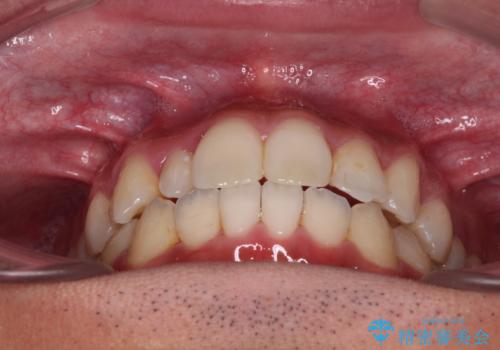

【モニター】左右のクロスバイトをインビザラインできれいに改善

下顎の歯列弓に対して上顎歯列弓がやや小さく、側方の歯を中心にクロスバイトが見受けられました。

クロスバイトの改善は、インビザラインの場合歯髄壊死のリスクや咬み合わせが改善しきらないリスクがあるため、ワイヤー矯正をお勧めすることが多いですが、患者様の希望によりインビザラインにて矯正治療を行うこととしました。

後方に隠れていた上顎前歯は矮小歯であるため、矯正治療の途中でオールセラミッククラウンを装着し、左右対称の大きさでの仕上がりを目指すこととしました。